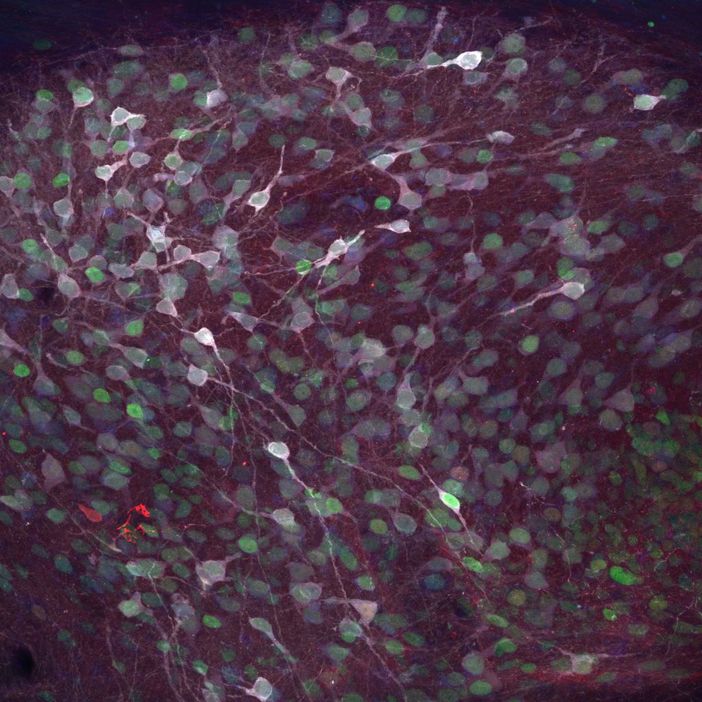

Il progetto finanziato mira a sviluppare e personalizzare un portfolio di prodotti a base di cellule staminali per gruppi di pazienti o singoli pazienti, con particolare attenzione alle malattie di Parkinson e Huntington. Integrando la tecnologia delle cellule staminali, genomica e bioingegneria, e mediante studi preclinici, l’obiettivo è sviluppare in provetta i neuroni ottimizzati degenerati nelle due malattie insieme a cellule complementari, da combinare in trapianti capaci di rispondere alle specifiche necessità terapeutiche dei singoli pazienti.

Inoltre, i neuroni trapiantati saranno migliorati nella loro capacità di riformare i circuiti perduti, così da aumentare il recupero funzionale post-trapianto. Un’innovazione consisterà nel modellizzare la formazione e ricostruzione dei circuiti umani in un sistema 3D in vitro, completamente umanizzato e bioingegnerizzato. Questo approccio permetterà di studiare, come mai finora, i fattori cellulari e molecolari che controllano l'integrazione corretta e funzionale dei neuroni umani. La ricerca genererà anche neuroni la cui attività può essere autoregolata o modulata in base alle esigenze individuali dei pazienti e doterà le cellule prodotte di meccanismi che, da una parte, le proteggono dalla patologia e dall’altra attenuano la malattia nel cervello malato.